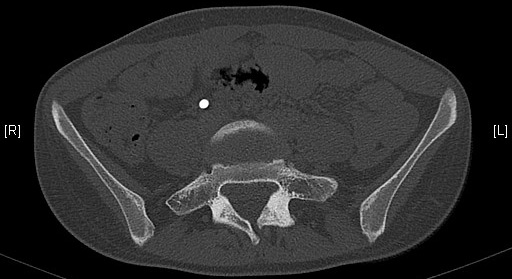

Scanner

Néo-articulation transverso-sacrée droite